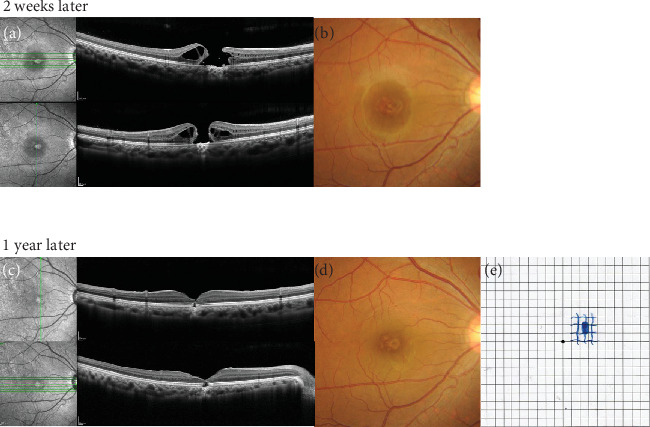

Introduction: Accidental retinal injuries caused by lasers without appropriate eye protection are not rare; most cases are unilateral. We report the case of a medical nurse who sustained bilateral foveal damage through indirect exposure to a picosecond dermal laser. Case Presentation: A 23-year-old nurse working in a cosmetic surgery clinic was using a picosecond KTP/Nd:YAG laser for tattoo removal. Because the procedure was complicated, she neglected the use of protective eyewear and experienced dazzle. Thirty minutes after starting the procedure, she developed central scotomas in both eyes. We examined her eyes the next day. Ophthalmologic examination revealed best-corrected decimal visual acuity (BCVA) of 0.6 in the right eye and 0.3 in the left eye. Spectral domain-optical coherence tomography showed a hyperreflective inner retinal layer with a lamellar defect and focal outer retinal detachment in the right eye; the left eye exhibited intra- and subretinal foveal hemorrhages. Injections of sub-Tenon's triamcinolone acetonide (12 mg/0.3 mL) in the right eye and intravitreal tissue plasminogen activator (30 μg/0.05 mL) in the left eye were administered on the same day. Two weeks later, a full-thickness macular hole (FTMH) was identified in the right eye; pars plana vitrectomy was required 6 weeks after initial presentation. Because the FTMH failed to close, a second procedure was performed 2 months later. One year after initial presentation, BCVA in the right eye had improved to 0.4. Although the FTMH remained closed, an outer retinal layer defect persisted. In the left eye, foveal hemorrhage resolved within 1 month of initial presentation. At the 1-year follow-up, BCVA in the left eye was 0.4; outer retinal layer disruption was evident at the central fovea. Conclusions: Continuous Nd:YAG laser exposure during cosmetic procedures likely caused the bilateral foveal damage observed in this case. All individuals using lasers must be aware of the importance of protective goggles.